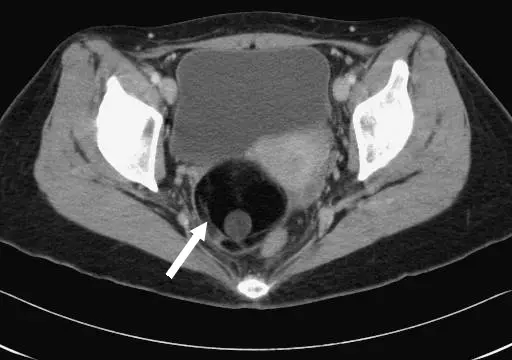

43 歲女性病人,健檢時發現 CA-199 升高,接受腹部影像檢查,上圖為骨盆處橫切超音波,下圖為 CT 最可能之診斷為何?

上圖:骨盆橫切超音波(Ultrasound, transverse view)

超音波標記顯示 "UB TR"(子宮 urinary bladder / uterus 橫切面)。影像中可見骨盆腔內有一個混合回音的佔位性病灶,其中包含:

- 一個高度強回音(hyperechoic)的內部結節,符合 Rokitansky 結節(dermoid plug,皮樣栓)

- 病灶內有強回音成分伴後方聲影(posterior acoustic shadowing),代表鈣化或毛髮/油脂等含脂成分

- 囊性部分與實性成分混合存在,整體呈現「冰山一角徵象」(tip of the iceberg sign)

- 強回音結節突入囊腔,排列符合典型畸胎瘤皮樣栓表現